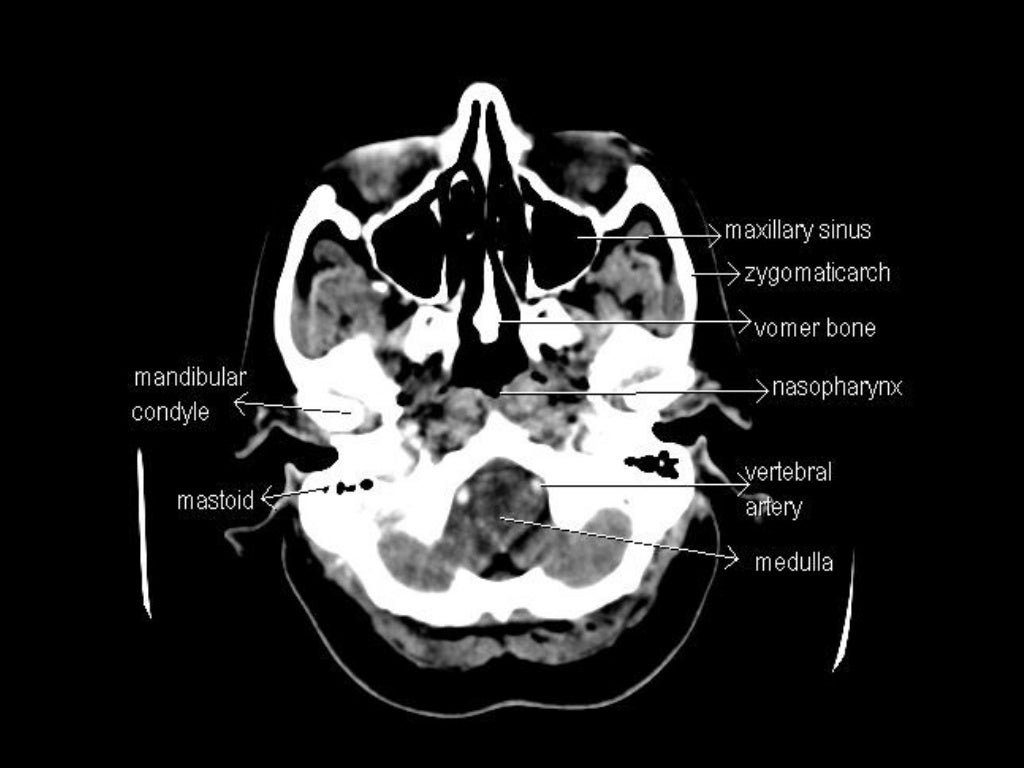

Ct Anatomy Study . It is performed with a higher radiation dose and larger dose of iv contrast, which helps to evaluate subtle areas of bowel inflammation. To get the full picture of abdominal anatomy, the examiner needs to move through the slices from cranial (proximal) to caudal (distal) while examining structures from their beginning. Radiological anatomy is where your human anatomy knowledge meets clinical practice. This case is used in 82. Explore detailed anatomical views and multiple modalities (over 8,900 anatomic structures and more than 870,000 translated. But instead of creating a flat, 2d image, a ct. What is a ct scan? Computed tomography (ct) scans are an extremely common imaging modality. A ct (computed tomography) scan is a type of imaging test. In this article, we will outline the basic principles. Annotated teaching ct head in standard and bone windows. This article lists a series of labeled imaging anatomy cases by body region and modality. Normal ct head with annotated and original images.

In this article, we will outline the basic principles. Radiological anatomy is where your human anatomy knowledge meets clinical practice. This case is used in 82. This article lists a series of labeled imaging anatomy cases by body region and modality. Annotated teaching ct head in standard and bone windows. Explore detailed anatomical views and multiple modalities (over 8,900 anatomic structures and more than 870,000 translated. Normal ct head with annotated and original images. A ct (computed tomography) scan is a type of imaging test. Computed tomography (ct) scans are an extremely common imaging modality. It is performed with a higher radiation dose and larger dose of iv contrast, which helps to evaluate subtle areas of bowel inflammation.